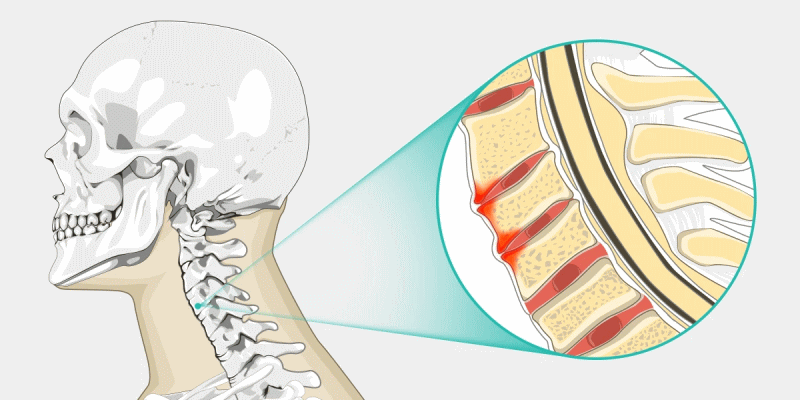

頚椎症とは、首の骨(7つの椎骨からなる頚椎)が、老化、過度のスポーツ、事故、悪い姿勢などのさまざまな要因によって、変形したり、劣化したり、棘が形成されたり、ズレたりするため、神経、脊髄、血管が圧迫され刺激を受けて、首や肩、腕や手に痛み(凝り)、痺れなどが出る疾患です。

変形性頚椎症は、悪姿勢、老化、スポーツ、事故による損傷、長年の生活習慣などによって頚椎が変形し、首、肩、腕、指などに痛み(凝り)を感じるようになります。

この変形性頚椎症から、状態が悪化していくと「頚椎症性神経根症」「頚椎症性脊髄症」になります。

頚椎症性神経根症は、頚椎の変形などによって神経根が圧迫されたために、首、肩、腕、指などに痛み(凝り)、痺れ、脱力を感じるようになります。症状は多くの場合、片側に現れます。

頚椎症性脊髄症は、頚椎の変形などによって脊髄が圧迫されたために、肩、腕、指、足などに痛み(凝り)、痺れが生じたり、手先の細かい作業、例えば、ボタンかけや箸を持つ動作が思うようにできなくなるような運動障害が生じます。